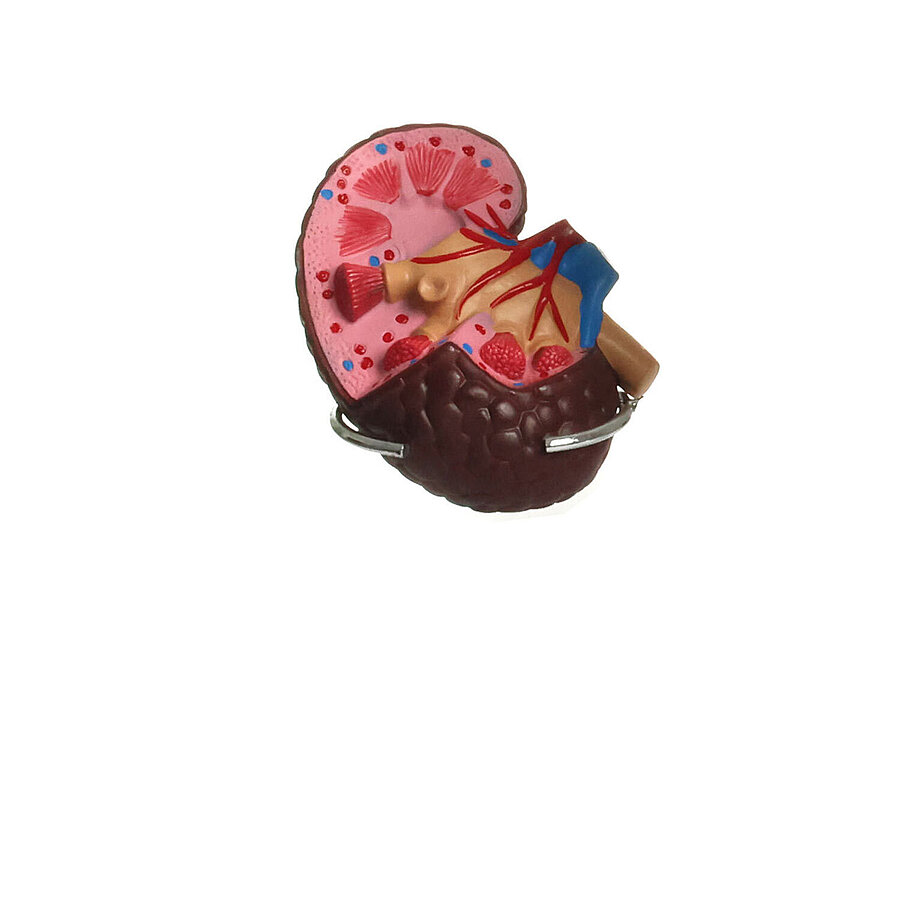

Modell der Hypertonie-Folgen

Zeigt die Folgeerkrankungen des Bluthochdrucks

Anatomische Strukturen sind aufwändig koloriert

Einzelne Organe bei Bedarf abnehmbar